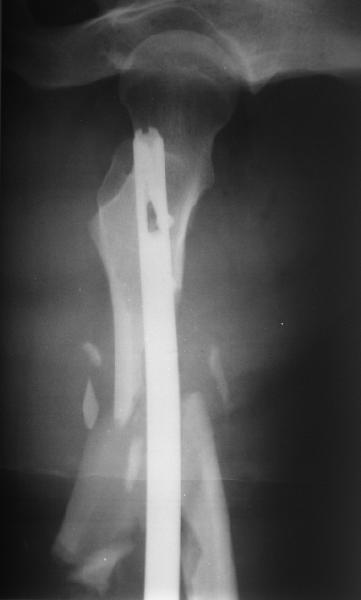

Мы бы не стали открывать, такие переломы срастаются, хотя бы и с

краевым дефектом. То есть если и удалять стержень потом, то сильно

попозже обычного. В приложении пример. Сразу после операции и через 11

мес. Понятное дело, пациент к тому времени давно и не хромал, и функция

колена была полная.